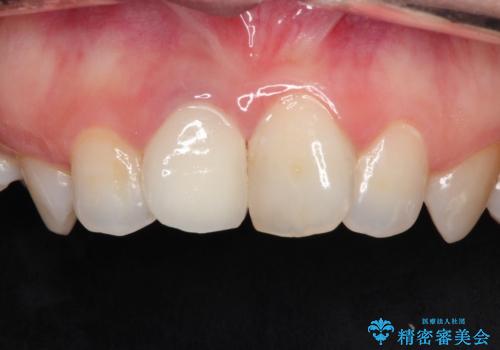

前歯の治療。再根管治療~セラミッククラウン

- 前歯の痛みを主訴に来院された患者様です。

再根管治療を行い、セラミックにて被せものを行いました。

症状も改善され満足して頂きました。